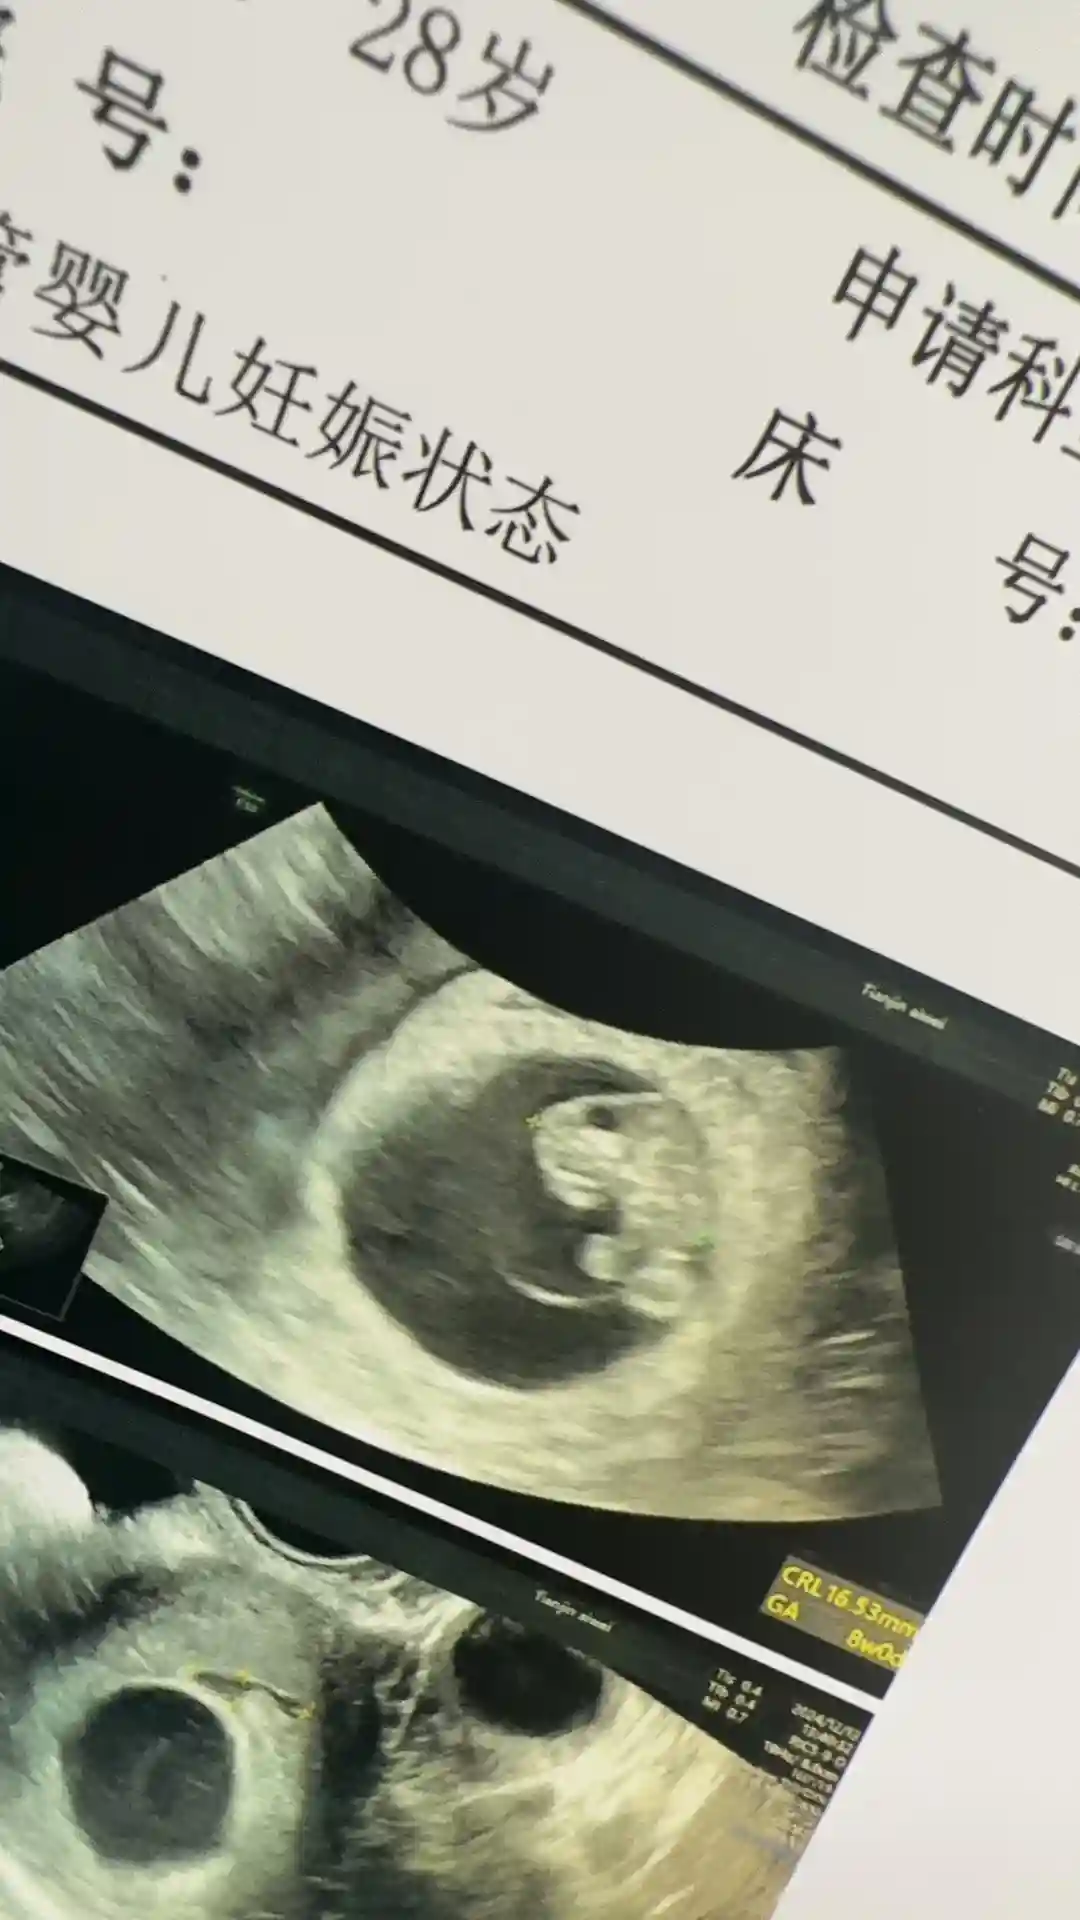

我的试管崽崽8周了

#天津爱维 #天津爱维医院